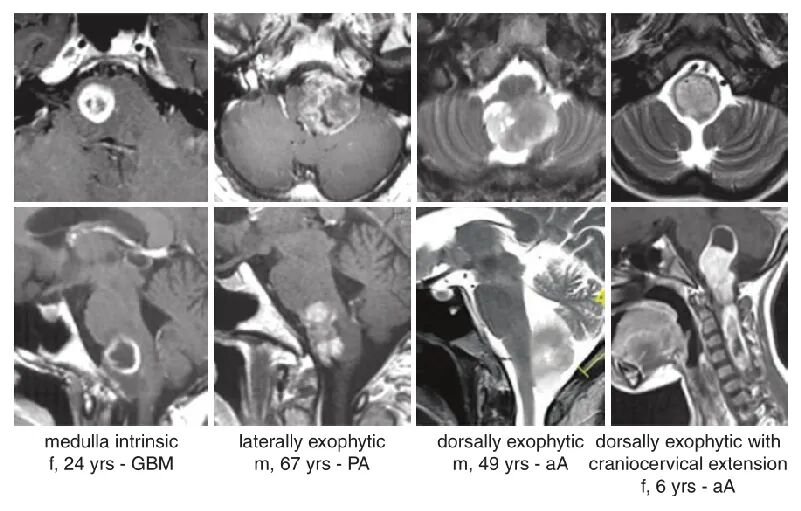

巴特朗菲教授总结临床中不同性质的延髓胶质瘤,将其分为4种类型:13个肿瘤局限于脑干下部,其他病变外生性生长,9个肿瘤主要生长在外侧,8个肿瘤向下方延伸从延髓进入脊髓。

MRI影像显示延髓区肿瘤部位与范围的代表性图像分为4列,对应4例不同患者:包括间变性星形细胞瘤(aA)、胶质母细胞瘤(GBM)、毛细胞星形细胞瘤(PA)。